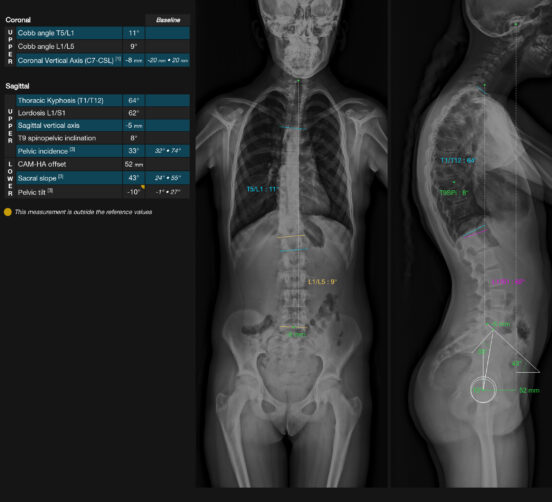

EOS-compatible measurements, with analysis report

TechCare Spine addresses the unique challenge of spinal medical imaging. The spine has significant anatomical complexity, and its central role in body posture and mobility must be leveraged by the latest deep learning advancements. This is why we provide radiologists and orthopedic surgeons with TechCare Spine, a tool for automatic measurements adapted to EOS imaging, offering significant time and productivity savings.

PELVIS : Pelvic version | Pelvic incidence | Sacral slope

SPINE : Coronal balance (CVA) | Sagittal balance (SVA) | Cyphosis T1-T12 | Heel T9 | Lordosis L1/S2 | Cobb angle | Gravity axis

INTUITIVES OUTPUTS showing frontal and profile views together